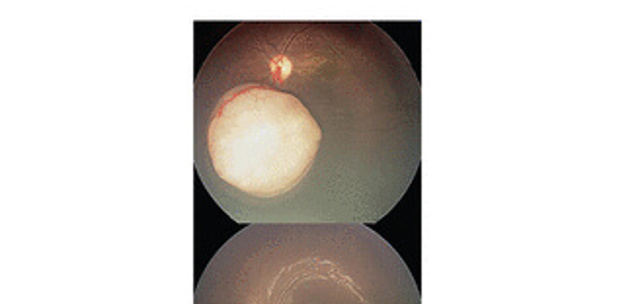

App detection of leukocoria